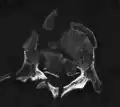

A burst fracture of L4 as seen on CT